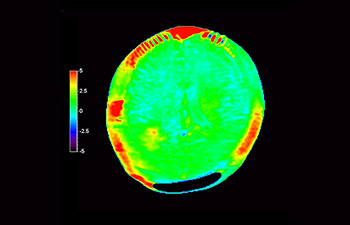

Brain imaging for glioblastoma recurrence

with 3D APT